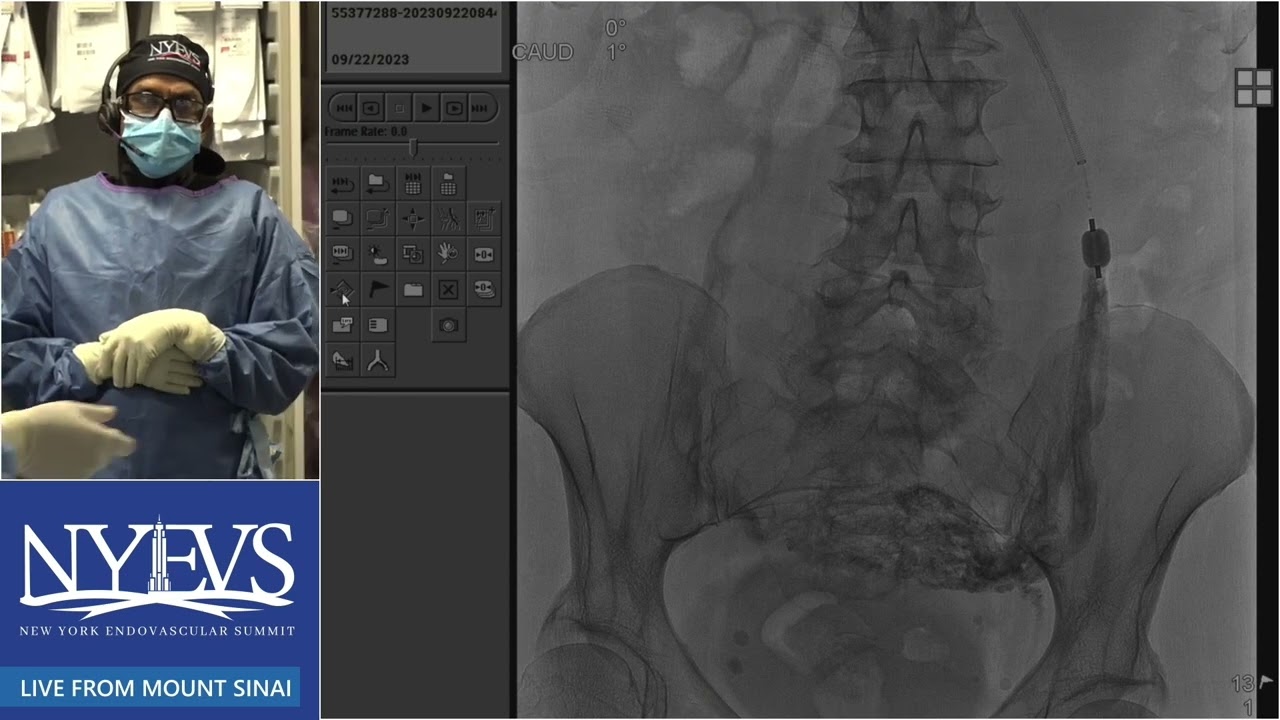

Pelvic venous disease can lead to vulvar varicosities, pelvic congestion or lower limb varicose veins

Varicose veins on the medial and posterior aspects of the thigh are usually caused by incompetent ovarian veins

Gluteal as well as vulvar varicosities, are often caused by reflux in the internal iliac veins.

Embolization with coils, plugs or liquid embolic agents is a minimally invasive way to treat this problems with low risks and excellent clinical results